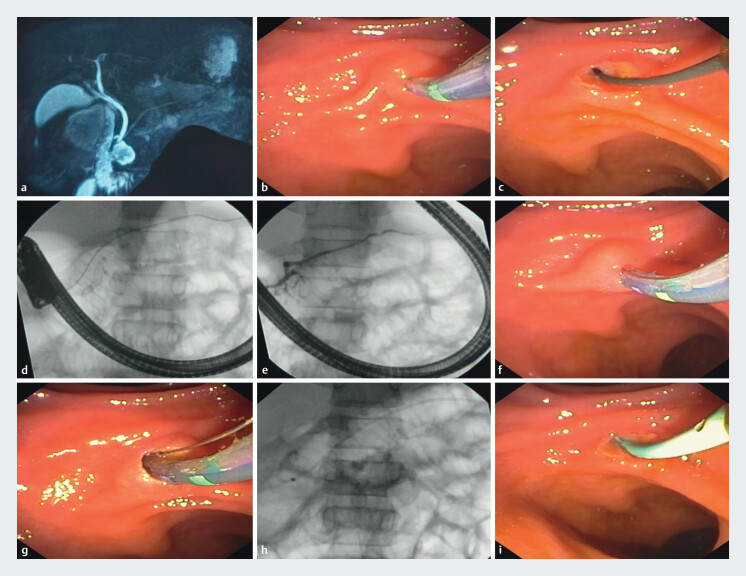

背景与研究目的:由于复发性急性胰腺炎(RAP)患者胰腺分裂(PD)的频繁复发,小乳头内治疗的成功率变化很大。因此,我们评估了成功的内治疗的有效性和预测因素。患者和方法:这是一项前瞻性观察研究,RAP患者接受小乳头括约肌切开术和预防性支架置入治疗PD。技术上的成功是小乳头插管和手术的顺利完成。主要和次要结局分别是疼痛复发的改善,视觉模拟评分(VAS)较基线减少50%,12个月时慢性胰腺炎(CP)的发生。通过逻辑回归评估成功的预测因素。结果:94例患者,中位年龄(四分位数间距)29.5岁(23.7-40.2岁);大多数男性(62例[65.9%])成功接受了体内治疗。87例(92.5%)患者的典型临床表现为腹痛。65例患者(69.1%)达到了主要结局。内镜逆行胰胆管造影(ERCP)的平均次数为2次;88例患者(93.6%)技术成功。ercp术后胰腺炎是10例患者中最常见的不良事件(AE)(10.6%)。11例(11.7%)出现CP征象,平均随访时间12.8±1.3个月。吸烟(校正优势比[AOR] 0.027, P = 0.001)和ERCP后RAP复发(AOR 0.169, P < 0.001)的患者获得成功的endotherapy结果的几率较低。结论:在接受ae的69.1%的患者中,RAP小乳头内治疗可显著提高12个月VAS评分。11.7%的患者出现早期CP。(唯一标识符:CTRI/2019/05/019332)。

Background and study aims: Minor papilla endotherapy success rate is highly variable for pancreatic divisum (PD) among recurrent acute pancreatitis (RAP) patients due to frequent relapses. Therefore, we assessed effectiveness and predictors of successful endotherapy.

Patients and methods: This was a prospective observational study of patients with RAP who underwent minor papilla sphincterotomy and prophylactic stenting for PD. Technical success was minor papilla cannulation and successful procedure completion. Primary and secondary outcomes were improvement in recurrent episodes of pain with reduction in visual analogue scale (VAS) score > 50% from baseline and occurrence of chronic pancreatitis (CP) at 12 months, respectively. Predictors of success were assessed by logistic regression.

Results: Ninety-four patients, with median age (interquartile range) 29.5 years (23.7-40.2); the majority male (62 [65.9%]), successfully underwent endotherapy. Typical clinical presentation was abdominal pain in 87 patients (92.5%). The primary outcome was achieved in 65 patients (69.1%). The average number of endoscopic retrograde cholangiopancreatography (ERCP) sessions was two; technical success was achieved in 88 patients (93.6%). Post-ERCP pancreatitis was the most common adverse event (AE) in 10 patients (10.6%). Signs of CP were seen in 11 patients (11.7%) and mean follow-up period was 12.8 ± 1.3 months. Presence of smoking (adjusted odds ratio [AOR] 0.027, P = 0.001) and recurrent attacks of RAP after index ERCP (AOR 0.169, P < 0.001) had lower odds of successful endotherapy outcomes.

Conclusions: Minor papilla endotherapy for RAP significantly improved VAS scores at 12 months among 69.1% of patients with acceptable AEs. Early CP was seen in 11.7% of patients. (Unique identifier: CTRI/2019/05/019332).